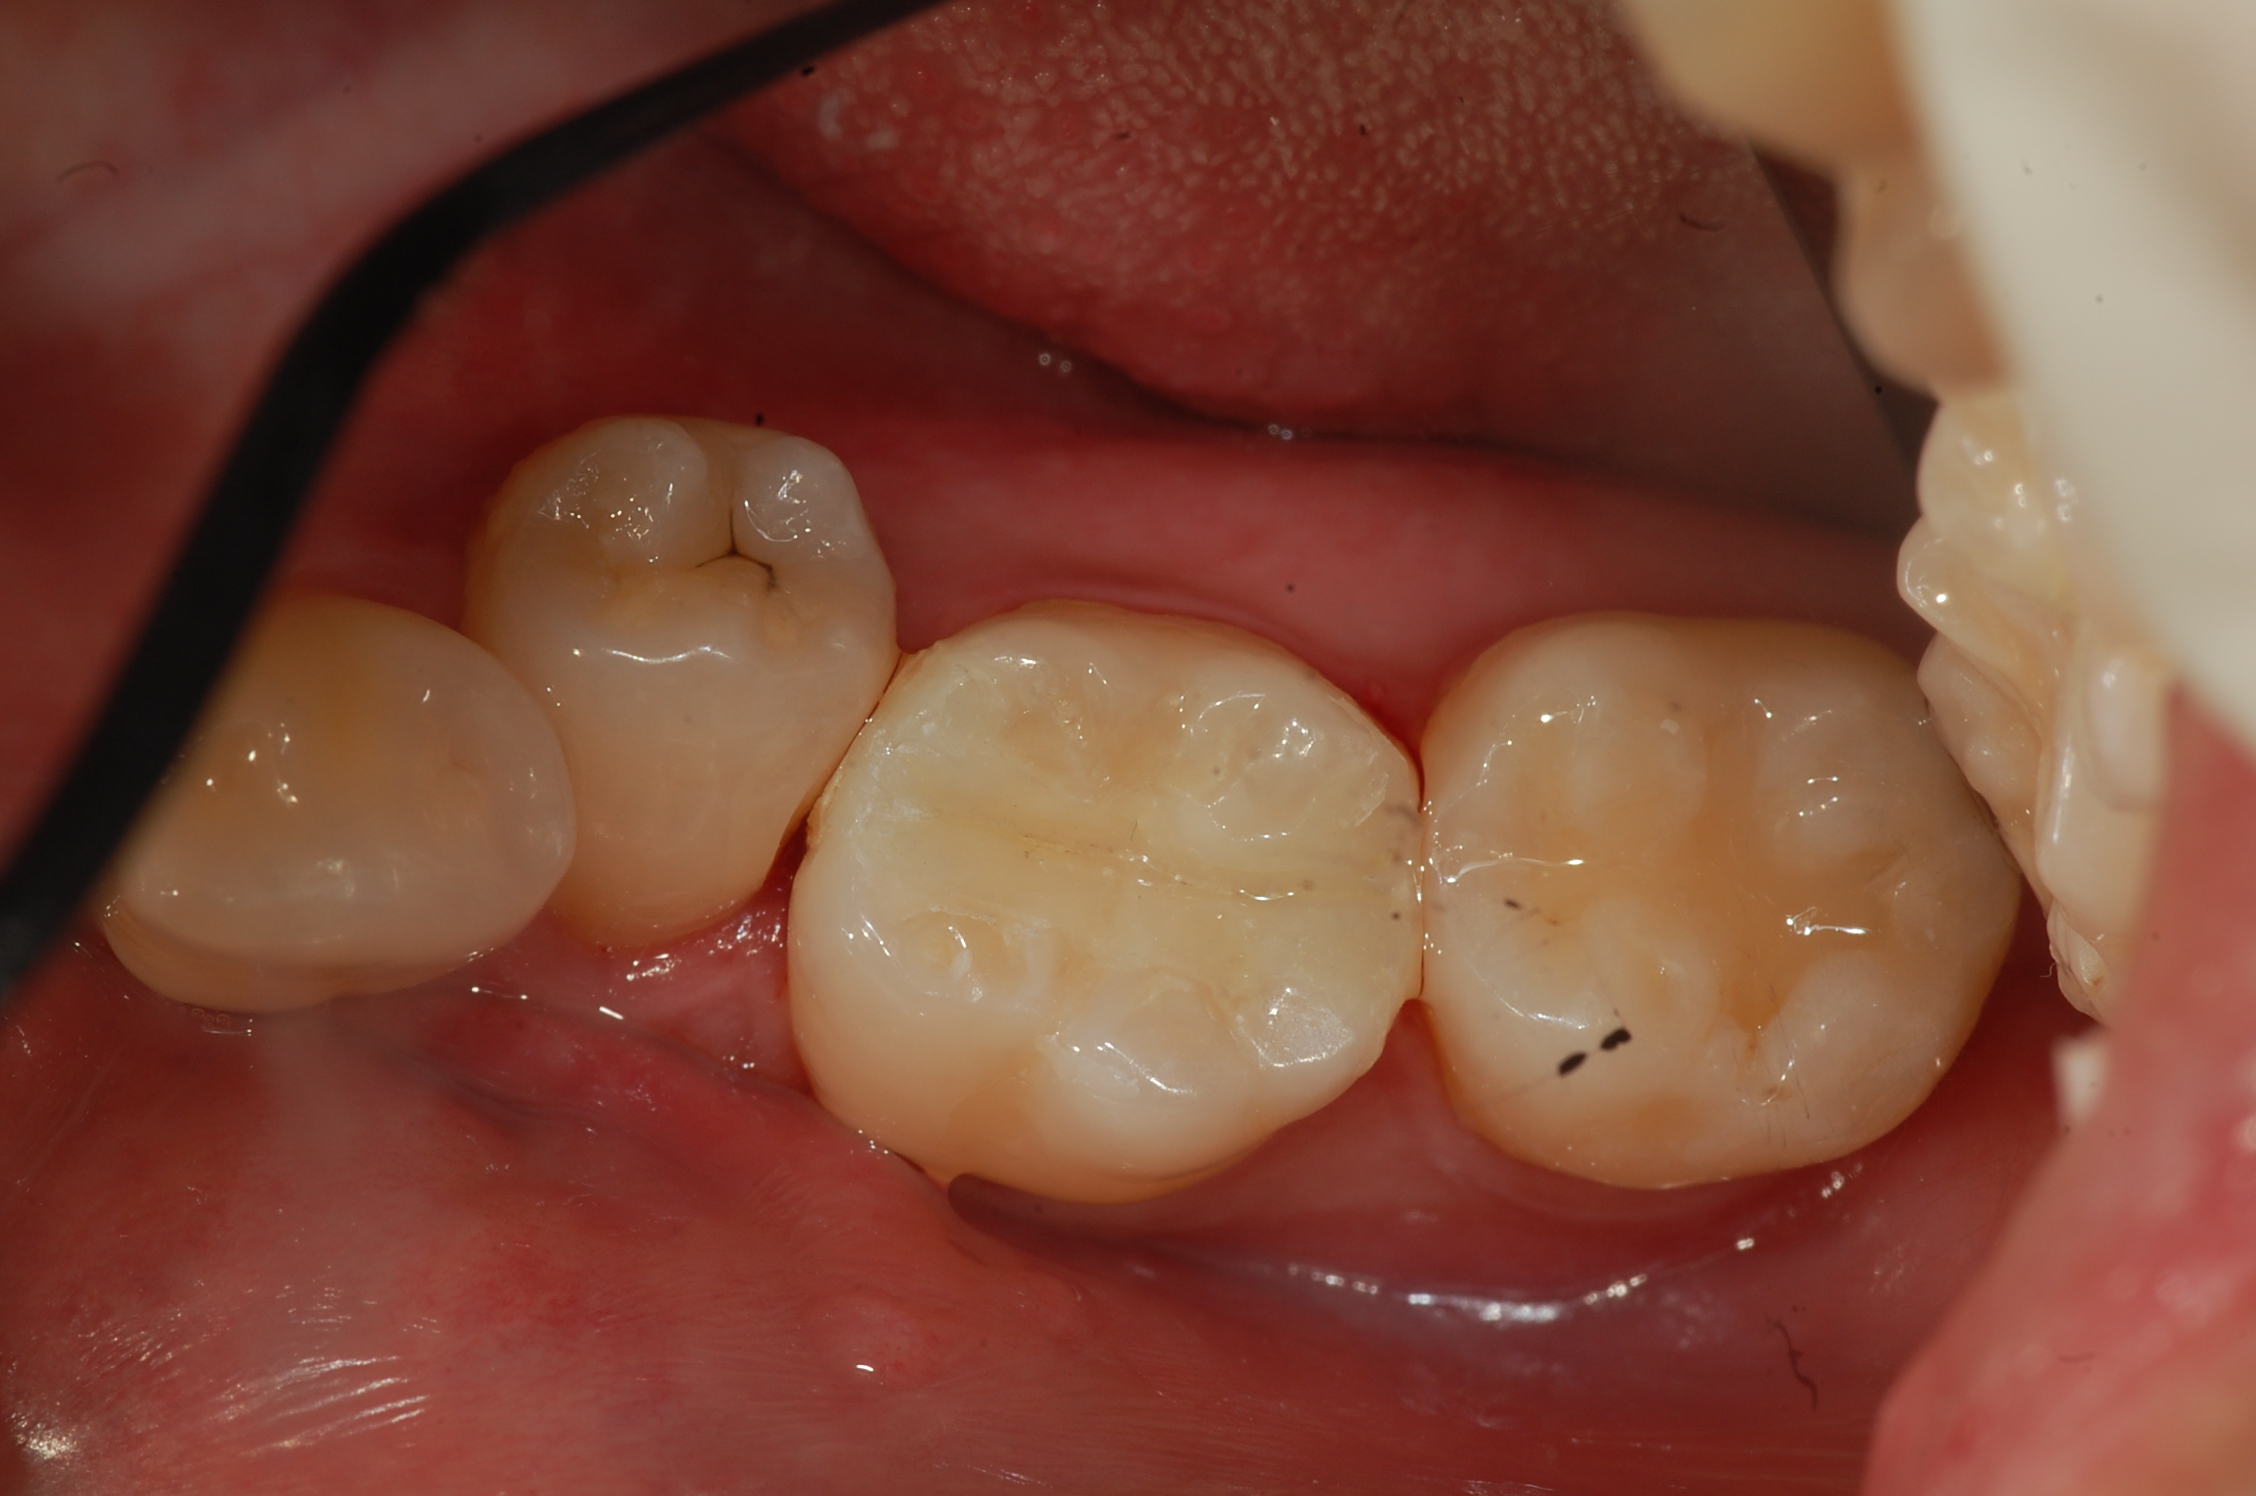

[보철,충치치료] 제목 : 하악 구치

인접면 충치 및 레진인레이